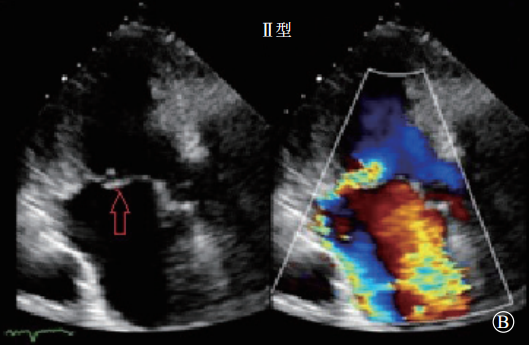

Ⅱ型:瓣叶活动过度的瓣膜功能失调(瓣膜脱垂,图3)。定义为一个或多个瓣叶活动度增加,瓣叶的游离缘在瓣叶关闭时超过了瓣膜口关闭时的平面,血流动力学结果提示为瓣膜反流,由于腱索断裂或延长,或者乳头肌断裂导致。

图3 Ⅱ型,过度瓣膜运动 A. 后叶过度运动,导致后叶脱垂,重度二尖瓣反流;B. 前叶过度运动,导致前叶脱垂,重度二尖瓣反流